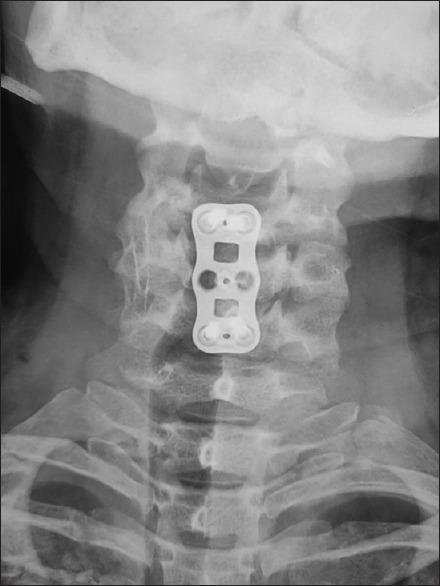

Non penetrating trauma to vertebral artery is a known complication in craniovertebral trauma. They are mainly reported with facet dislocations or injuries involving the foramen transversarium. Such a type of injury is rarely seen with flexion injuries. We report such a case leading to cerebellar stroke in a young male presenting to us with hemiparesis. A 43-year-old male presented to us 1 month post trauma after a motor vehicular accident with complaint of weakness of right half of the body since the trauma. He suffered blunt trauma to head and neck and complained of a flail right upper limb since trauma and weakness of the right lower limb which had partly improved. He was conservatively managed elsewhere. Radiographic investigations revealed complete occlusion of the right vertebral injury above the level of 6 cervical vertebra and flexion teardrop fracture of 5 cervical vertebra. He was managed conservatively for the vertebral artery injury (VAI) and corpectomy of C5 vertebra with anterior cervical plating and fusion. Such a rare type of injury can present with unexplained neurodeficit which needs appropriate radiological investigations for diagnosis before ascribing the cause to cord trauma. Hence, all high velocity motor vehicular accidents with associated fractures and neurodeficit should be screened for blunt VAIs.

椎动脉非穿透性创伤是颅颈创伤中一种已知的并发症。它们主要与小关节脱位或涉及横突孔的损伤有关。这种类型的损伤在屈曲性损伤中很少见。我们报告了一例年轻男性因偏瘫前来就诊,最终导致小脑卒中的病例。一名43岁男性在机动车事故创伤1个月后前来就诊,自创伤后一直主诉身体右侧无力。他头部和颈部遭受钝性创伤,自创伤后一直主诉右上肢连枷样摆动以及右下肢无力,不过右下肢无力症状有所改善。他在其他地方接受了保守治疗。影像学检查显示,右侧椎动脉在第6颈椎水平以上完全闭塞,第5颈椎屈曲泪滴样骨折。他因椎动脉损伤(VAI)接受了保守治疗,并对第5颈椎进行了椎体次全切除,同时进行了前路颈椎钢板固定和融合术。这种罕见类型的损伤可能表现为无法解释的神经功能缺损,在将病因归因于脊髓损伤之前,需要进行适当的影像学检查以明确诊断。因此,对于所有伴有骨折和神经功能缺损的高速机动车事故,都应筛查是否存在钝性椎动脉损伤。